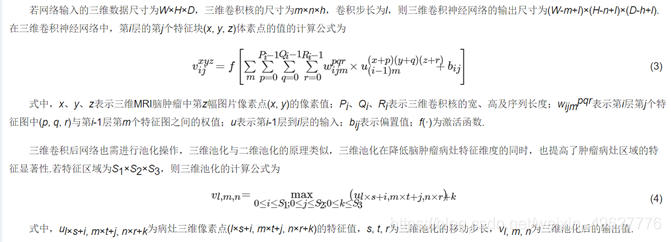

在深度神经网络中,网络的层数较深,不同层之间的神经元相互影响.若在网络的某一层数据发生抖动偏移,随着网络的加深数据抖动的问题会愈加强烈,从而影响模型的训练优化过程,归一化可有效缓解数据震荡的问题.目前常用的数据归一化方法有批量归一化(Batch Normalization, BN)、全局归一化(Group Normalization, GN)、权值归一化(Weight Normalization, WN)以及实例归一化(Instance Normalization, IN)等.在本实验中训练集和测试集的batch大小均设置为1,而BN、LN和WN均是针对于batch值较大的情况,而IN能够处理batch值较小的情况,因此采用IN对脑肿瘤数据进行归一化处理,在解决数据抖动的同时加快脑肿瘤检测网络的收敛速度.IN方法的示意图如图 5所示.

图 5 实列归一化方法示意图

图 5从N看过去是一幅幅脑肿瘤图片,从C方向看过去是脑肿瘤特征图的像素点.每11个竖着排列的小正方体组成的长方体代表一幅脑肿瘤图片的一个特征图.深色方块是一起进行归一化的部分,由此可以很清楚地看出IN是指单张脑肿瘤图片的单个通道单独进行归一化操作.